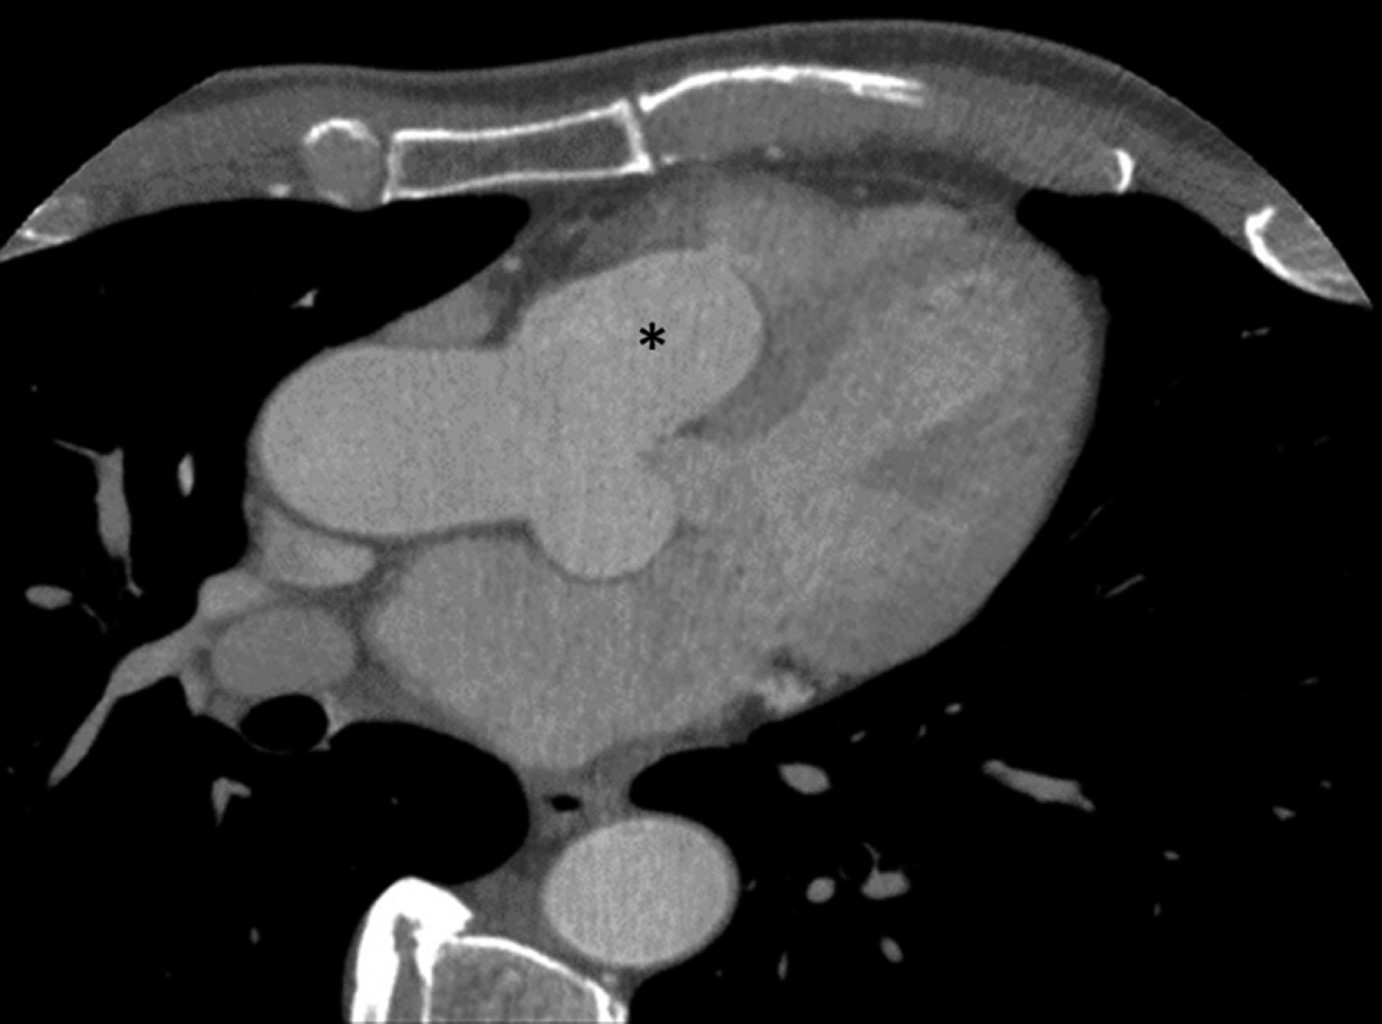

Los aneurismas del seno de Valsalva son dilataciones congénitas o adquiridas de la pared del seno aórtico a nivel justo por encima de las tres cúspides de la válvula aórtica, que pueden ser casos asintomáticos o fatales si se rompen, más frecuentemente hacia las cavidades cardiacas derechas. Estos casos son relativamente raros. Presentamos el caso de un varón de 72 años remitido por sospecha de soplo pulmonar. La evaluación reveló un aneurisma del seno de Valsalva derecho, que causaba compresión del tracto de salida del ventrículo derecho (TSVD). El ecocardiograma, la tomografía computarizada y el aortograma revelaron imágenes interesantes y evocadoras. El paciente recibió una reparación quirúrgica mid-cap. Este artículo revisa y discute la literatura actual y presenta el caso.

Figura 1